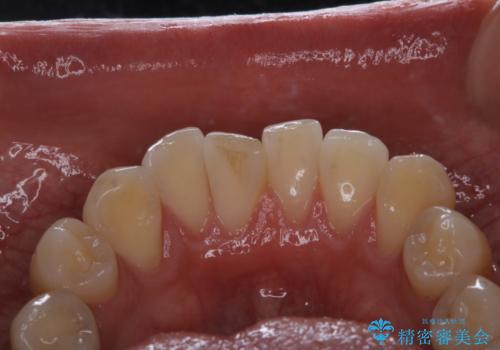

- コーヒーを毎日飲むので、どうしても着色がついてしまう。前歯の目立つ着色をきれいにとってほしいとのことでした。

PMTC60分コースを行いました。

PMTCは、歯に付着した汚れを除去していくため、着色が気になる場合にも行うことができます。ご自身でのセルフケアだけで着色を落とそうとすると、逆に歯を傷つけてしまったり、精密に汚れを除去できないこともあります。また、日常生活で着色しやすい飲食物を避けたりすることはストレスに感じてしまったり、あまり現実的ではありません。